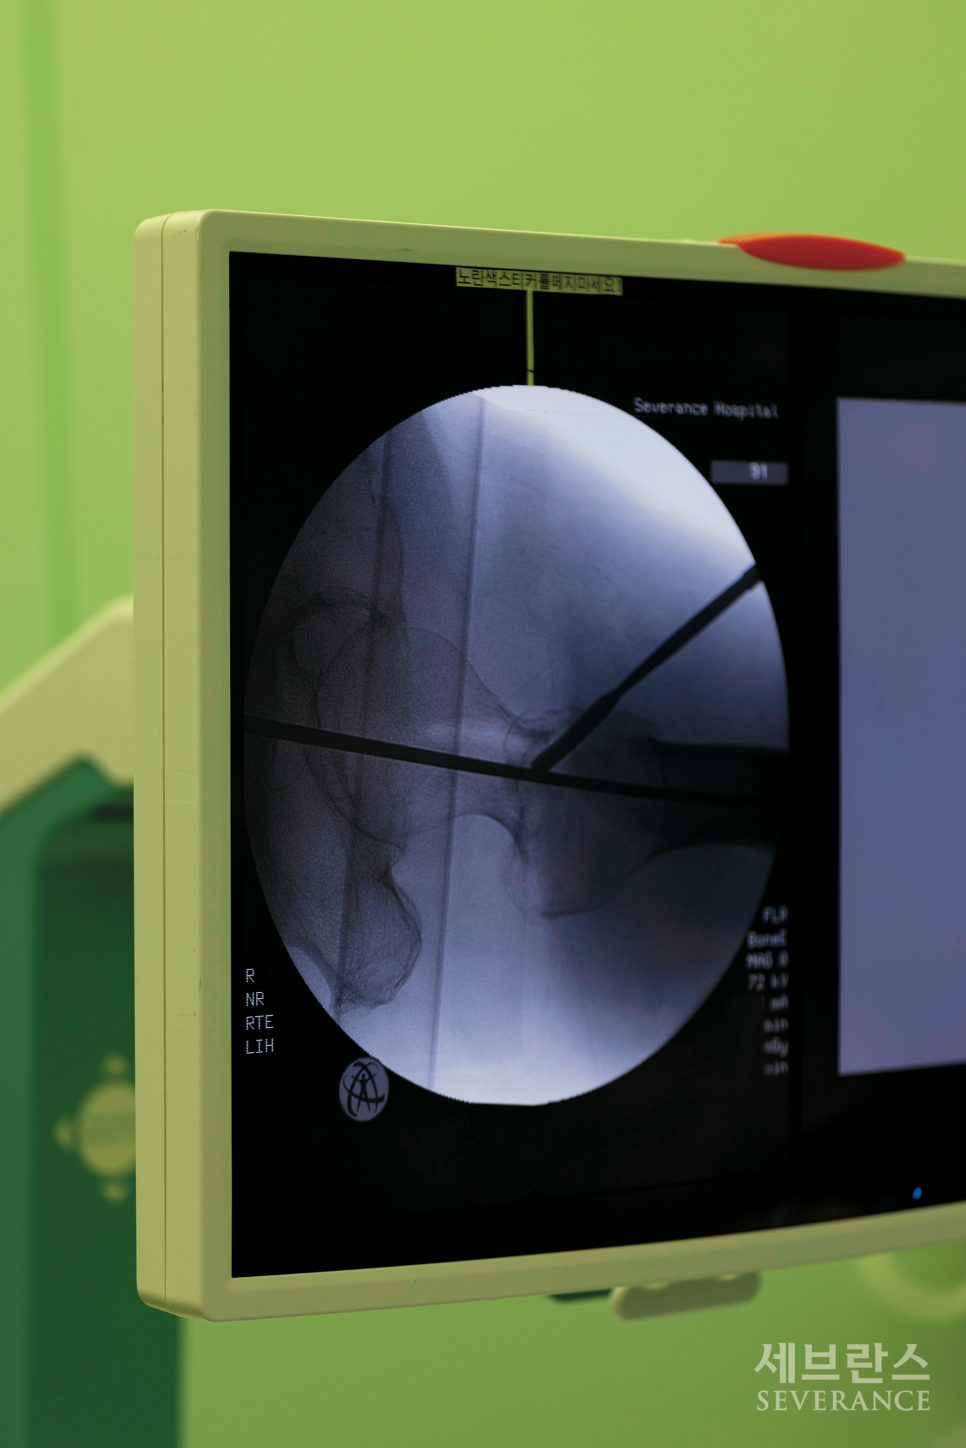

대퇴골 골절 수술은 일반적으로 다른 부위의 골절처럼 뼈를 붙이는 치료를 하고, 고령의 대퇴경부 골절 환자에서는 인공관절 치환술을 하기도 합니다. 전신 또는 척추마취가 필요하며 골절로 어긋난 뼈를 잘 맞춘 뒤 여러 금속 기구를 이용해 적절하게 고정시킵니다.(금속판, 금속정) 많은 환자들이 수술 후 초기에 뼈가 잘 붙고 있는지 궁금해합니다. 골유합에 필요한 시간은 개인마다 차이가 있으며, 보통 3-6개월 정도 걸립니다. 수술 후 외래진료에서 일반 방사선검사를 시행해 고정된 뼈가 움직이는지, 삽입된 금속에 문제가 없는지 등을 확인하는데, 이때 뼈가 잘 고정되어 있고 금속 주위에 문제가 없으면 대부분 골유합이 잘 이루어집니다.